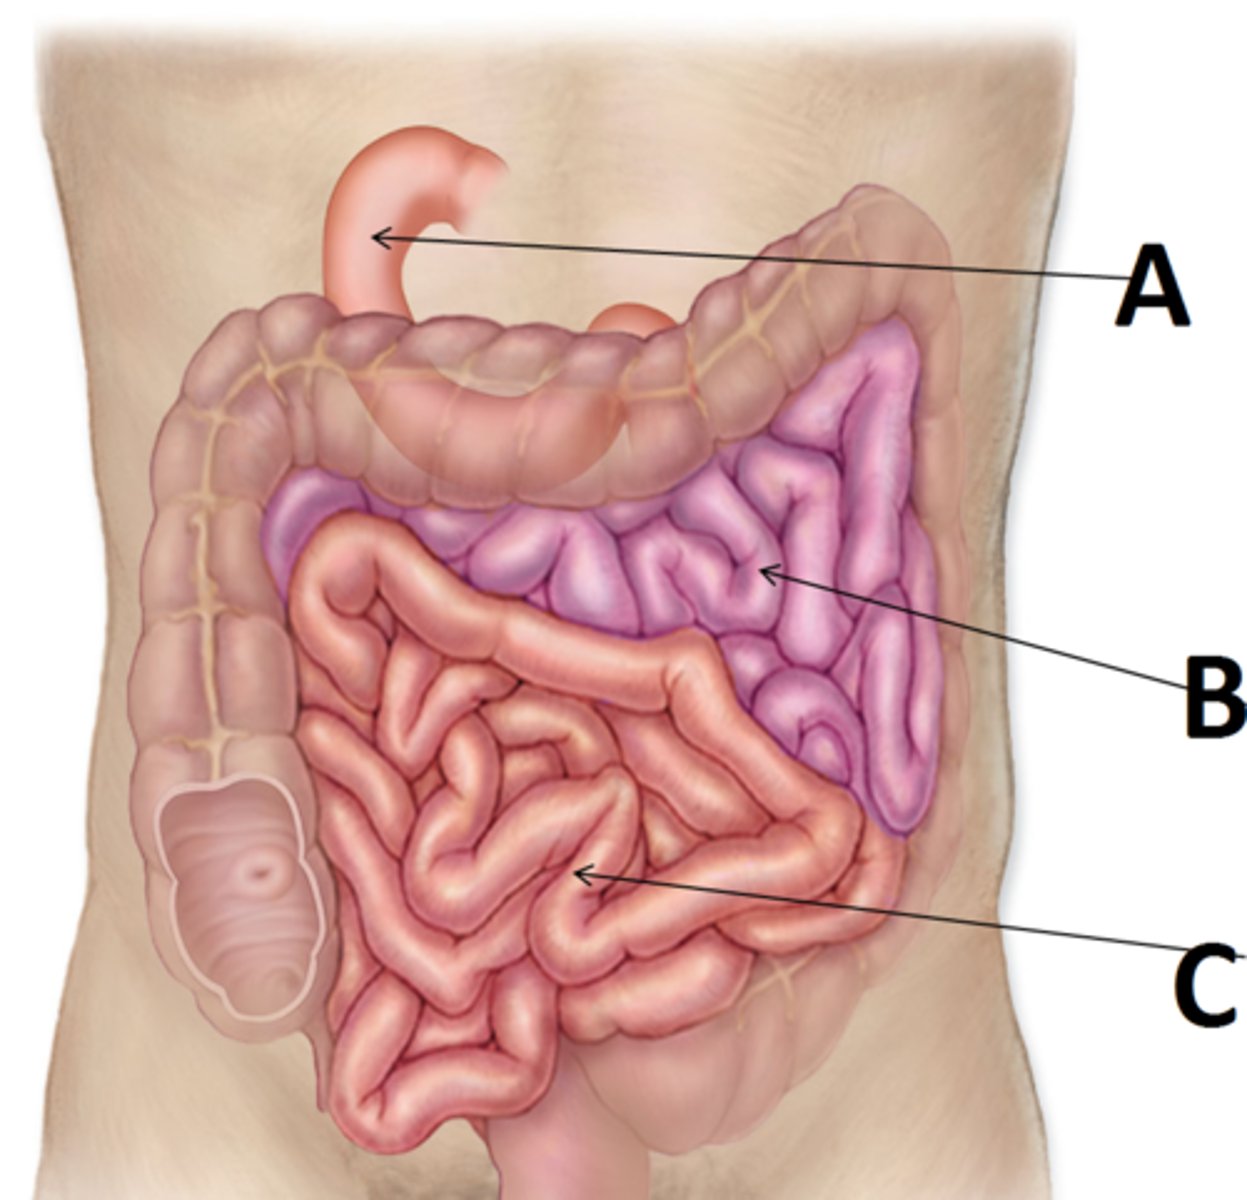

small intestine

duodenum

A

jejunum

B

ileum

C